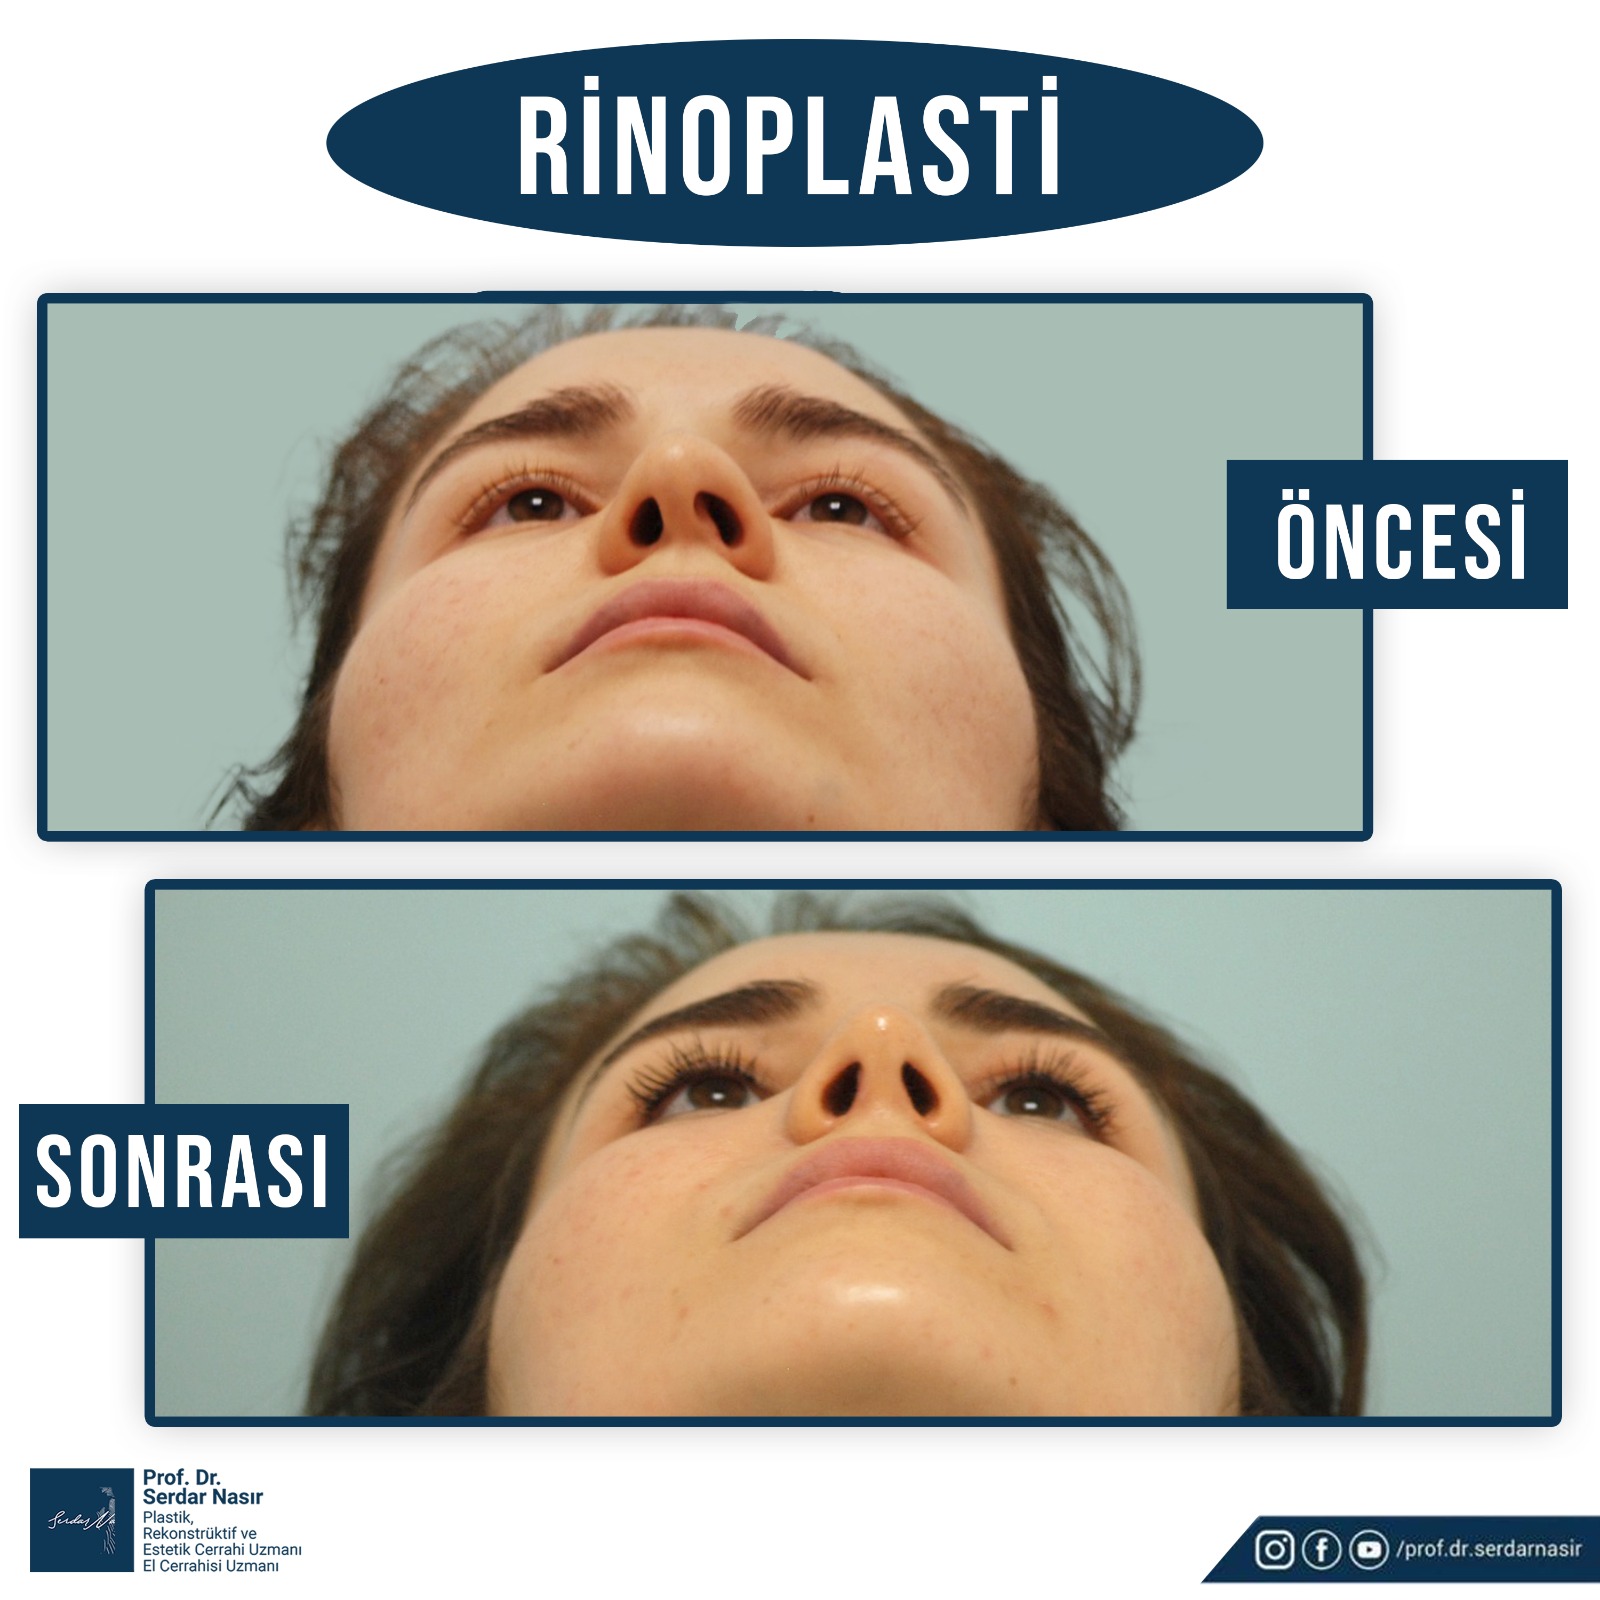

Estetik burun ameliyatı bana göre plastik cerrahinin en zor ameliyatlarından biridir. Çünkü burunda estetik olarak güzel bir sonuç elde etmeye çalışırken aynı zamanda fonksiyonel sonuçta yani hastanın nefes alıp vermesininde bozulmaması ve hatta sorun varsa düzeltilmesi gereklidir. Bu nedenle oldukça dikkatli yapılması gereken ameliyatlardır. Şu da bir gerçektir ki en çok revizyon dediğimiz ilk ameliyattan sonra tekrar bazı küçük deformitelerin veya hoşa gitmen bazı ayrıntıların düzeltilmesinin yapıldığı ikinci ve bazen üçüncü ameliyatlar en çok bu grupta saptanmaktadır. Bu nedenle özellikle ilk ameliyatın başarılı şekilde yapılması bu revizyon olasılığını azaltacaktır. Yine de estetik burun ameliyatı olmayı planlayan bir kişi her zaman için bir revizyon olasılığını akılda tutmasını öneririm.

Burun ameliyatları kapalı veya açık olarak iki teknikle yapılmaktadır. Plastik Cerrahlar hem kendi deneyimleri hemde hastanın ihtiyacına göre bu tekniklerden birini seçmektedir.

Kişisel tecrübeme gelince ameliyat sonrası şişliklerin daha az olması, dokuları daha az travmatize etmesi gibi düşüncelerle ilk planda kapalı tekniği tercih etmekteyim. Ancak hastanın burun deformitesi özellikle burun ucuna yönelik ağırlıktaysa veya çok detaylı bir cerrahi girişim yapılacaksa açık tekniği tercih etmekteyim. Ancak tecrübelerime göre kapalı teknik ile açık tekniğe gerek kalmadan bir çok hastanın sorunu çözülebilmektedir.